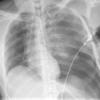

3 tension